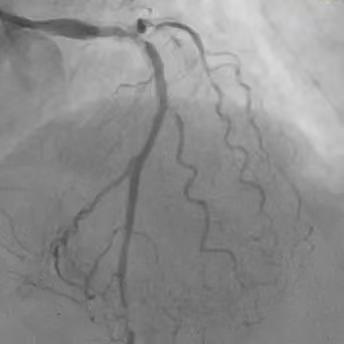

患者74岁,10年前因胸痛诊断为冠心病,在外院放过支架,但当时医生即明确告知家属,血管最严重的“总开关”左主干的地方钙化分叉,处理起来太危险,只是把难度相对不高的血管放了支架。近年来患者间断胸闷、胸痛,伴有心衰下肢肿胀,辗转来我院。冠脉CT显示冠脉严重钙化,因此安排冠脉造影检查。 ![]() ![]() 术前CTA提示左右冠支架术后且左主干重度钙化 (主干没有支架) 冠脉造影

![]() ![]() ![]() 左右冠脉造影:右冠脉支架远段已完全闭塞,旋支远端完全闭塞,前降支中远段重度狭窄,左主干重度钙化分叉。 手术策略